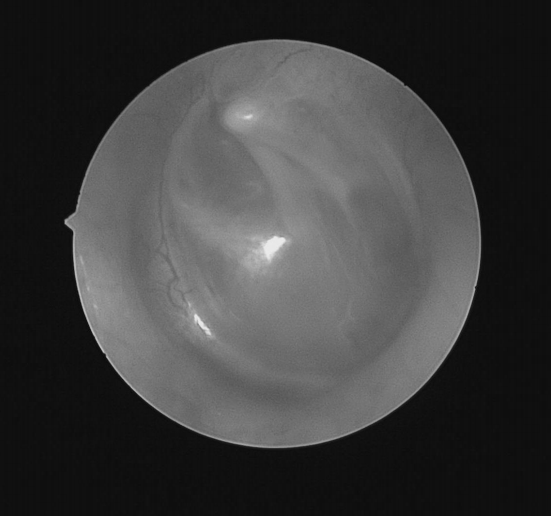

耳内镜检查:分泌性中耳炎(右)

双耳鼓膜完整,右侧鼓膜内陷明显,右侧鼓室可见积液